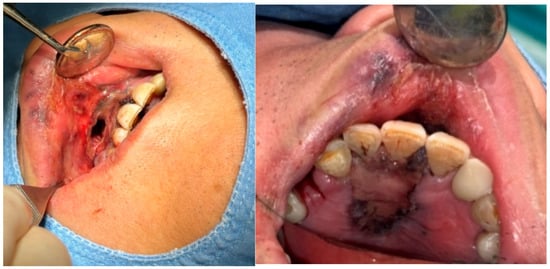

A 69-year-old male patient presenting with severe toothache 10 days before admission and melena 3 days before admission was admitted to the Infectious Disease Department of Kyung Hee University Hospital in the Republic of Korea in March 2025. The patient reported worsening toothache in the right upper gingiva with right facial swelling that began 5 days after a dental implant surgery at the upper right first premolar. Subsequently, the patient underwent incision and drainage at a local dental clinic one day before admission because of periodontitis that had spread to the facial area, as confirmed through the patient’s medical history. The patient had diabetes and was taking hypoglycemic agents. He had undergone coronary artery bypass grafting (CABG) for myocardial infarction 13 years previously. Additionally, he had undergone a prostatectomy for prostate cancer 2 years ago. He had been continuously taking clopidogrel (an antiplatelet agent) since undergoing CABG. The right buccal area of the face was swollen. Dental examination revealed a space abscess around the upper right first premolar (Figure 1). Panoramic dental X-ray showed that the implant fixture was placed in the alveolar bone of the upper right first premolar, and the external part has been removed (Figure 2). The implant fixture at the upper right first premolar was removed and irrigation and drainage were performed at the upper right first premolar and the vestibular area of the upper right second incisor, canine, and first premolar. The initial vital signs were blood pressure, 124/73 mmHg; pulse rate, 87 beats/min; respiratory rate, 20 breaths/min; temperature, 36.5 °C, oxygen saturation level, 98% on room air. Laboratory examination revealed a white blood cell (WBC) count of 6.23 × 109/L (83.0% neutrophils) and a C-reactive protein (CRP) level of 417.0 nmol/L. The aspartate aminotransferase, alanine aminotransferase, and alkaline phosphatase levels were 46, 57, and 97 IU/L, respectively. The serum creatinine level was 1.08 mg/dL and the BUN was 40 mg/dL. The serum sodium level was 129 mEq/L. Plasma level of glycated hemoglobin was 13.5%. Chest computed tomography revealed a mass-like lesion in the left lung with multiple small nodules in both lungs. Two sets of blood cultures were performed on the day of admission using BD Bactec Plus Aerobic/F and BD Bactec Plus Anaerobic/F bottles and a Bactec FX Instrument (Becton Dickinson, Sparks, MD, USA). The patient underwent esophagogastroscopy, which revealed active bleeding from multiple duodenal ulcers and subsequently received hemostatic treatment. A gastrointestinal bleeding dynamic computed tomography (CT) scan showed a liver abscess at S2/3 (3.1 cm) (Figure 3a) with focal septic thromboembolism in the left hepatic vein (Figure 3b). Chest CT revealed mass-like consolidation and air densities in the left upper and lower lobes, along with multiple irregular nodules with ground-glass opacities in both lungs (Figure 3c,d).

Figure 1. Clinical photography of initial dental examination. The external part of implant at upper right first premolar had already been removed at local dental clinic. Irrigation and drainage were performed at the upper right first premolar and the vestibular area of the upper right lateral incisor, canine, and first premolar. The implant fixture at the upper right first premolar was removed.